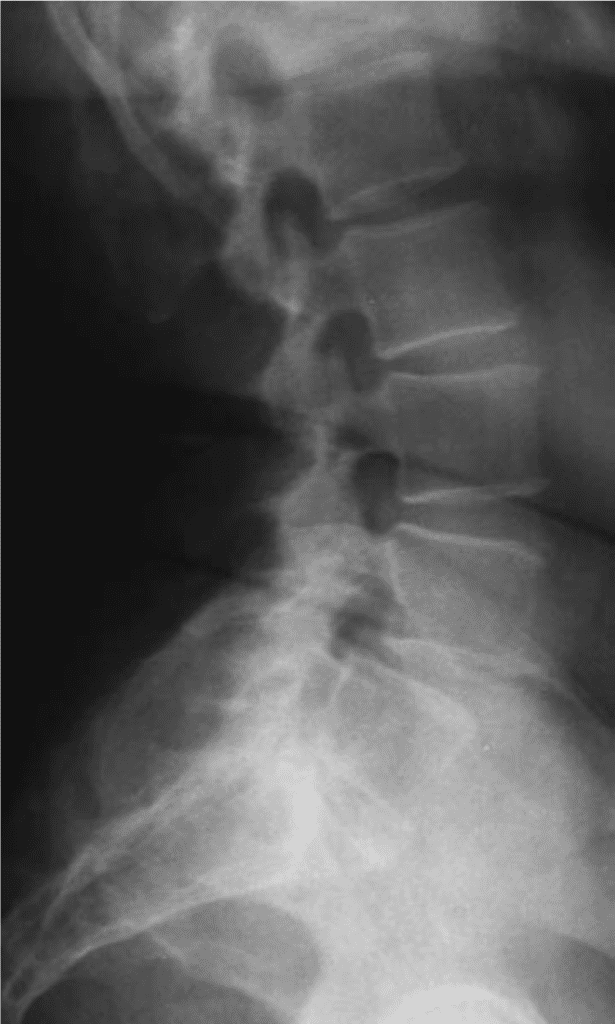

Patient de 70 ans se plaignant de lomboradiculalgies mal systématisées. Une radiographie est réalisée.

Que visualisez-vous sur cette radiographie ?

Radiographie de la colonne vertébrale, vue de face.